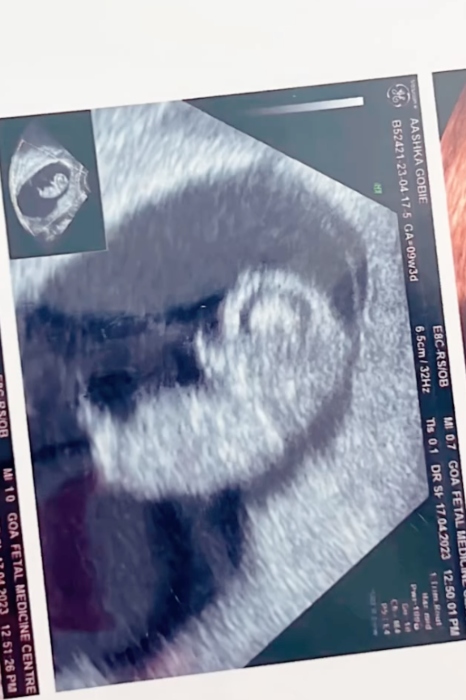

Aashka Goradia is pregnant with her first child. Aashka and her husband Brent Globe married on December 1, 2017, in Goa. After six years of 'happily ever after' and exploring the world together, Aashka and Brent are all set for nesting. Recently, the mommy-to-be, Aashka Goradia shared glimpses of her first sonography and also shared her experience of seeing her first child, nurturing in her womb.

On May 23, 2023, Aashka took to her Instagram handle and posted a cutesy video compilation of her beautiful pregnancy moments. The clip started with the parents-to-be, Aashka and Brent's picture as they enjoyed their time on a cruise. Followed by first glimpses of Aashka's pregnancy scan. In one of the pictures, Aashka flaunted her baby bump in a black dress.

Alongside it, the mommy-to-be Aashka expressed her happiness on seeing her child nurturing and growing inside her womb. She called it magical, and her note can be read as:

"So thankful it was magical to see this one for the first time It reminded me of all the beautiful days together with @ibrentgoble. Each day is magical. Filled with joy, excitement and fears but the anticipation to see this little one covers all fears. Dear husband - we have grown, everything is more special. To all the parents, including mine - thank you! It’s truly the greatest ride!"